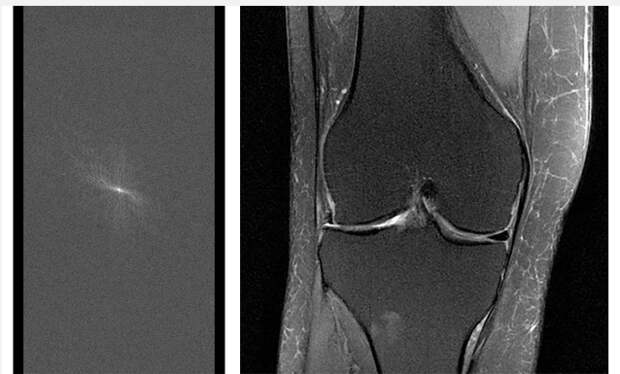

By using less data, the fastMRI project aims to produce reliable scans up to 10x faster than today.